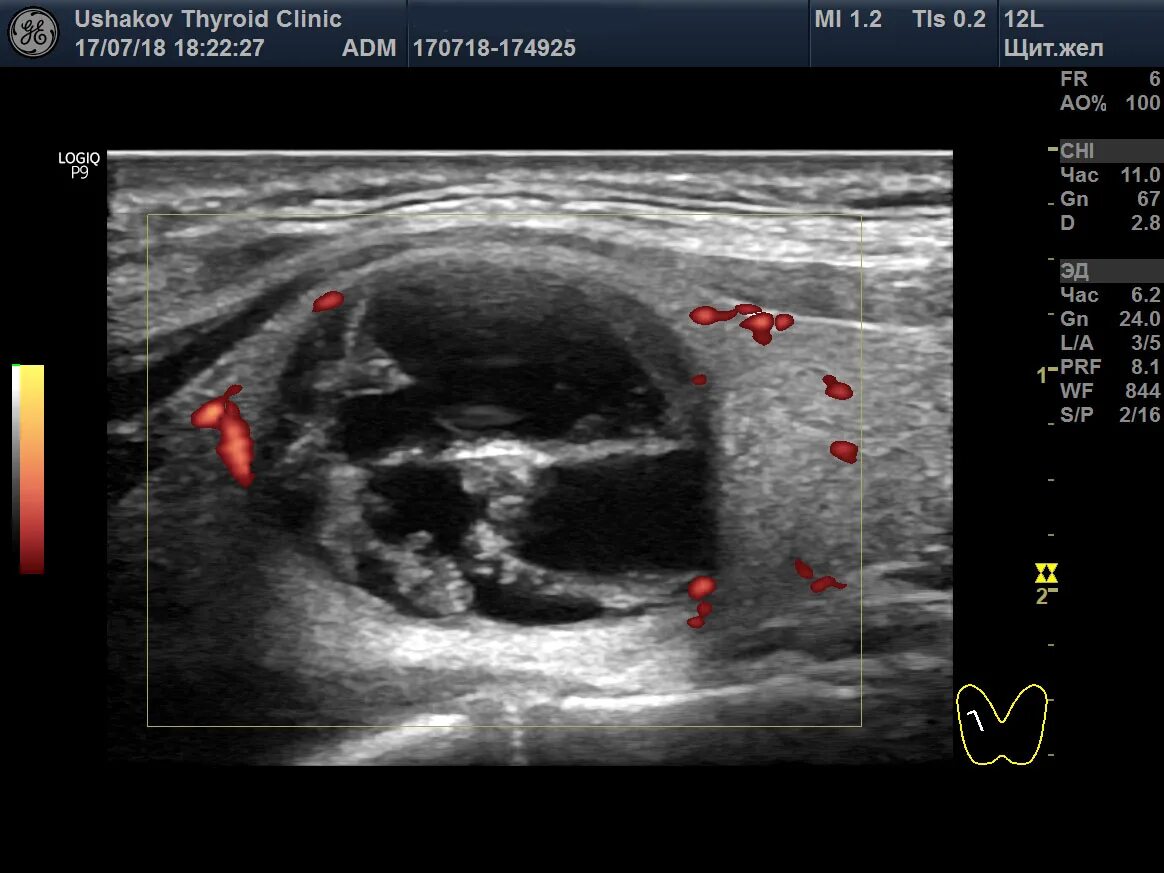

Узи аномалий